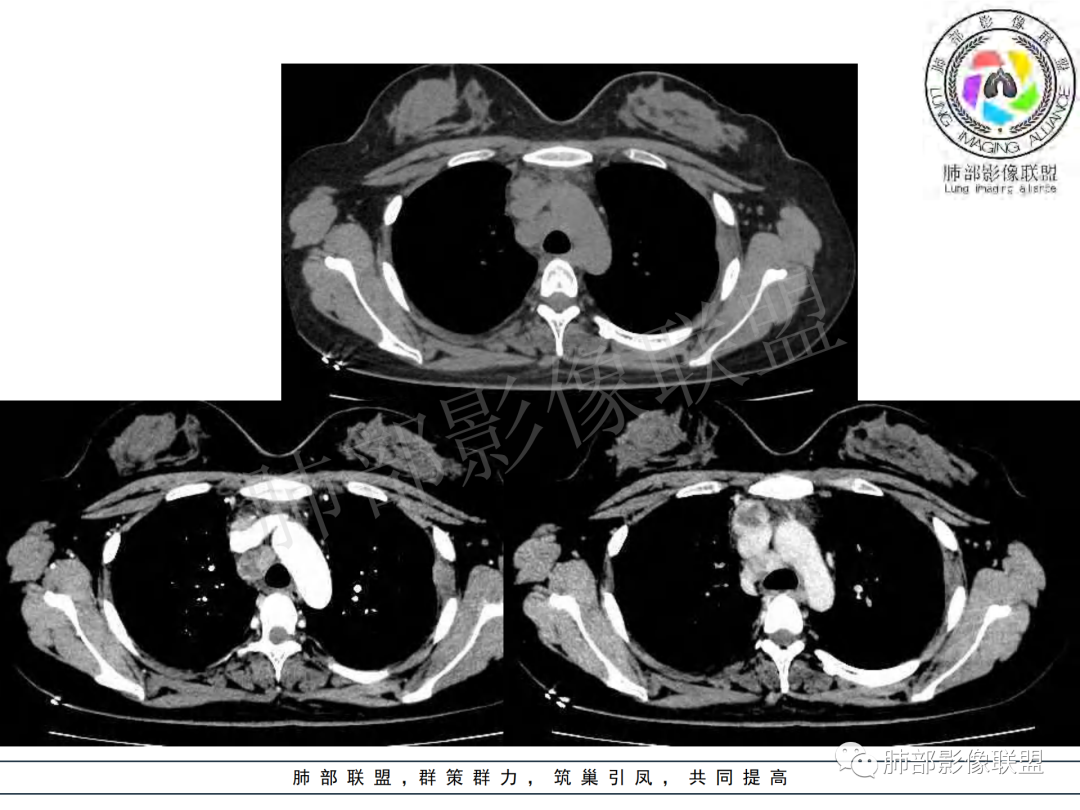

纵隔多组及右侧肺门多发肿大淋巴结,部分融合,不均匀强化,内见斑片状坏死区及环状强化,后者坏死边界尚清晰,肺门区肿大淋巴结与肺组织边界不清,年轻女性,8个月病史,发热首发症状,考虑淋巴结核并向肺内侵及(破溃?),鉴别淋巴瘤

女,20,病程长达8月,发热、胸痛、右侧胸腔积液病史。胸部CT:右肺门旁不规则肿块影,右中间支气管腔内结节,纵隔多发淋巴结肿大;强化不均匀,灶性坏死灶,环形强化;右侧少量胸腔积液并局部肉芽肿样突起。年轻女性,长病程,多部位,考虑慢性炎症,结核?鉴别肿瘤。

年轻女性 大支气管占位恶性三件套 高强化 内部可见无强化区,无强化区与强化区内边界大部分不清晰,类癌、粘表、腺样囊性癌。首先考虑粘表   其次需要鉴别的有结核   这么大片的坏死 结节病可能性小

青年女性,发热、胸痛、右侧胸腔积液病史,病程8个月。曾多次抗炎后均有好转。CT:右肺门旁肿块影,双侧胸膜结节,纵隔多发淋巴结肿大,边缘模糊;增强渐进性明显强化,纵膈淋巴结较彻底坏死灶,边缘环形强化。考虑结核,鉴别恶性肿瘤。

女性,20岁。高热、畏寒。右肺上叶近肺门区不规则肿块,周围斑点、片小结节影伴肿大淋巴结,肿块包绕并突入右主支气管腔内,增强后肿块不均匀强化,淋巴结环形强化中心低密度,考虑结核。

纵隔肺门及两侧胸膜强化结节,支气管管腔不通畅。结核能解释临床及影像,就是强化有点猛,这个妖怪真不好说。恶性如类癌/高级别黏表/恶性间皮也要考虑。

本例患者,年轻女性,慢性病程,多次抗感染治疗效果不佳,实验室检查示白细胞及中性粒细胞不高,不支持普通细菌感染,虽然肺泡灌洗液X-Pert检测阴性,结合患者胸部CT结核感染亦不能排除,胸部CT主要表现为右侧肺门及纵隔淋巴结肿大,仔细观察不难发现右中间支气管内新生物凸向管腔内,增强扫描,右肺门(10R)及纵隔淋巴结(2R,4R)明显不均匀强化,内部呈不规则低密度无强化区,被周边高强化区包绕(环形强化)的特点,首先应当想到纵隔淋巴结结核诊断。淋巴结分布亦不符合肺部恶性肿瘤迁徙途径。

马尔尼菲篮状菌感染也可表现为多处环形强化肿大淋巴结,但常见于易感人群。